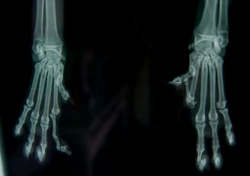

diagnose wordt gesteld door het bevoelen van de kniegewrichten

(palperen)en soms zijn er röntgenfoto's nodig. In sommige

gevallen is het mogelijk de patella met de hand uit de groeve te

duwen; dit mag normaal gesproken niet kunnen.